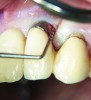

Fig 1. A deep pocket of 7 mm prior to active periodontal therapy.

Figure 1

Fig 2. Following periodontal regenerative therapy, the tooth with a 3-mm probing depth, which facilitates maintenance.

Figure 2

Following active therapy, probing depths of 4 mm or less (Figure 1 and Figure 2) and the absence of bleeding on probing contribute to improved health and stability. Increasing probing depths should alert the therapist to identify etiology and determine whether active periodontal therapy is warranted. The absence of bleeding on probing is a strong predictor of stability, and although the presence of bleeding does not always result in attachment loss, it remains an important parameter to evaluate.14 Bleeding on probing is also an important parameter for assessing implant health during maintenance. Serino et al15 evaluated 27 patients with 19 dental implants over 5 years. Patients were seen every 6 months and they concluded that bleeding on probing was a good predictor for attachment loss and disease progression around the implants (Figure 3).